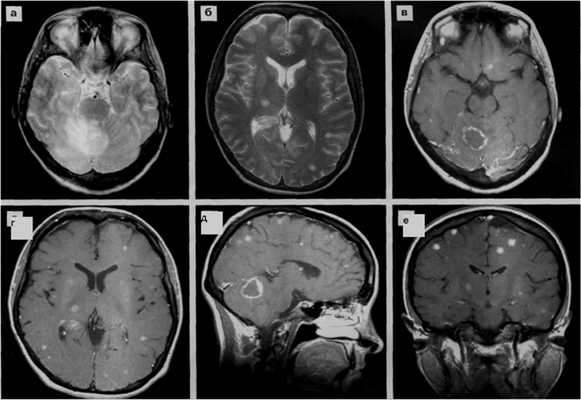

а-аксиальная КТ головного мозга

б,в,г -аксиальные МРТ в режимах Т2, Т1

аксиальная Т1 с контрастным усилением

относительно симметричные диффузные или мультифокальные гиперинтенсивные изменения белого вещества в перивентрикулярной области и семиовальном центре с неровными краями, без масс-эффекта, не накапливающие контраст, либо более мелкие асимметричные очаги в белом веществе и базальных ядрах.